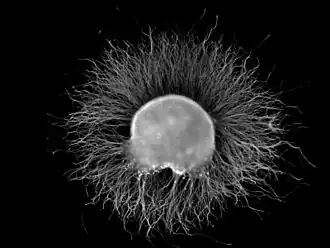

Ganglion

A ganglion (pl.: ganglia) is a group of neuron cell bodies in the peripheral nervous system. In the somatic nervous system, this includes dorsal root ganglia and trigeminal ganglia among a few others. In the autonomic nervous system, there are both sympathetic and parasympathetic ganglia which contain the cell bodies of postganglionic sympathetic and parasympathetic neurons respectively.

Ganglia are primarily made up of somata and dendritic structures, which are bundled or connected. Ganglia often interconnect with other ganglia to form a complex system of ganglia known as a plexus. Ganglia provide relay points and intermediary connections between different neurological structures in the body, such as the peripheral and central nervous systems.